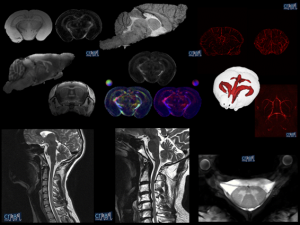

– Expo images du cerveau

– Interventions scolaires